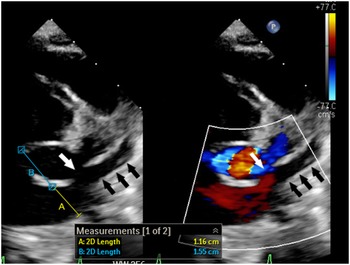

Figure 1. 2-Dimensional echocardiogram with and without colour shows dilated coronary sinus ostium (A) with short septal length (B) and partially unroofed coronary sinus (black arrows). The unroofed segment is depicted with the white arrow.

Despite the advancement in surgical and transcatheter treatments, the prognosis of extensive primary pulmonary vein disease continues to be poor with an estimated mortality rate of 40–50% at 1 year. Reference Vanderlaan, Rome, Hirsch, Ivy and Caldarone1–Reference Khan, Qureshi and Justino4 When the atrial septum is intact, transcatheter pulmonary vein intervention requires creating an atrial septal defect which is challenging and carries substantial risks, especially in young infants. Reference Srinivas, Singla, Reddy, Nagesh and Nanjappa5 Moreover, the presence of the dilated coronary sinus further complicates the safety of the procedure as the septal length becomes significantly shorter (Fig 1). Reference Muller, Backhoff and Schneider6 In the described case, the coaxial system of the 5-Fr JR 4 guide, 4-Fr Jr 2 catheter, and guidewires allowed us to cross the unroofed coronary sinus into the left atrium and the stenotic common left pulmonary vein, with relative ease. In addition, the 5-Fr guide catheter (with an outer diameter of 1.67 mm) enabled us to deploy the stent without the need to exchange for a long sheath. Due to the antiproliferative effect, drug-eluting stents slow the progression of pulmonary vein disease when compared with bare-metal stents. Reference Khan, Qureshi and Justino4 Although exclusive balloon angioplasty is an attractive treatment option, the likelihood of complete occlusion is higher when compared with stent placement. Reference Buiatti, von Olshausen and Martens7 As our patient has a common left pulmonary vein, occlusion would result in complete loss of the physiologic function of the entire left lung which could lead to persistent pulmonary hypertension. Additionally, the presence of a stent will ease transcatheter recanalization should future occlusion occurs as the stent is easily visualized by fluoroscopy. For the future management of the patient, we are planning to perform serial dilation, and we anticipate the need to intentionally fracture the stent to accommodate for somatic growth if a larger diameter is needed. Reference Khan, Qureshi and Justino4